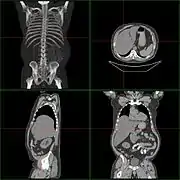

| Комп'ютерна томографія гепатомегалії | |

Якщо при перкусії розмір печінки по linea medioclavicularis dextra[1] перевищує 12 см чи пальпують ліву долю печінки в епігастральної області, відзначають збільшення печінки. Важливо виключити опущення печінки (наприклад, при хронічному обструктивному захворюванні легень чи надиманні правої легені) чи розташування в правому верхньому квадранті інших тканин (збільшений жовчний міхур, пухлина нирки чи кишки). Розміри печінки краще визначати за допомогою комп'ютерної томографії (КТ) або ультразвукового дослідження (УЗД). Важливо оцінити контури і рисунок тканини органу; збільшення тих чи інших ділянок тканини; «кам'яниста» консистенція передбачує наявність пухлини; біль при пальпації каже про запалення (гепатит) чи швидке збільшення розмірів органу (недостатність правих відділів серця, хвороба Бадда — Кіарі, гостра жирова дистрофія при синдромі Рея, гестозі вагітних).